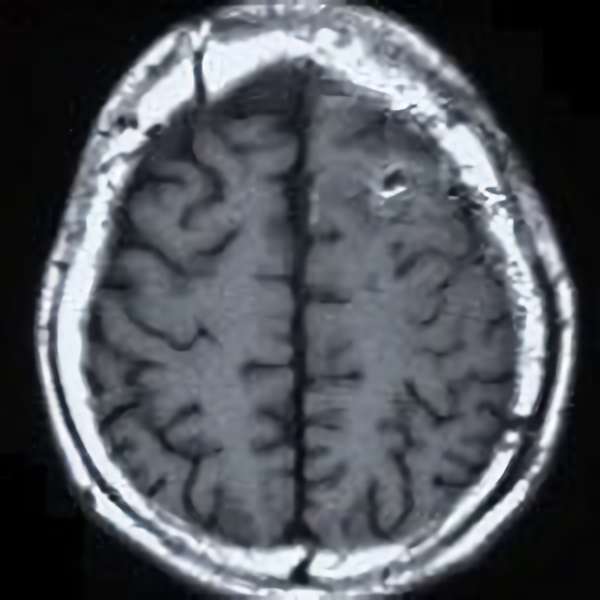

No.452 手術前

No.452 手術中

No.452 手術後

全治。

脳血管撮影により完全除去が確認された